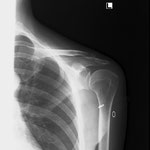

〇右鎖骨骨折

病院で手術の日程が決まっていましたが、保存的治療を希望されので当院で固定と経過観察をしました。(セカンドオピニオンとして整形外科医を紹介し同意)

骨折部位の転位がありますが正しい固定と注意深い経過経過観察、固定時期から積極的に周囲の血行を保つことにより経過良好で完治しました。

数多くの鎖骨骨折を診てきましたが、転位はひどくても正確な固定が維持できれば、かなりの成果があげられます。

今までに偽関節等で再度手術になった方はいらっしゃいません。

ちょうど暑い季節だったので、毎回固定を外し体をボディーソープで清拭しました。持参の下着に着替えてから再固定をしたのでストレスが少なかったと思います。